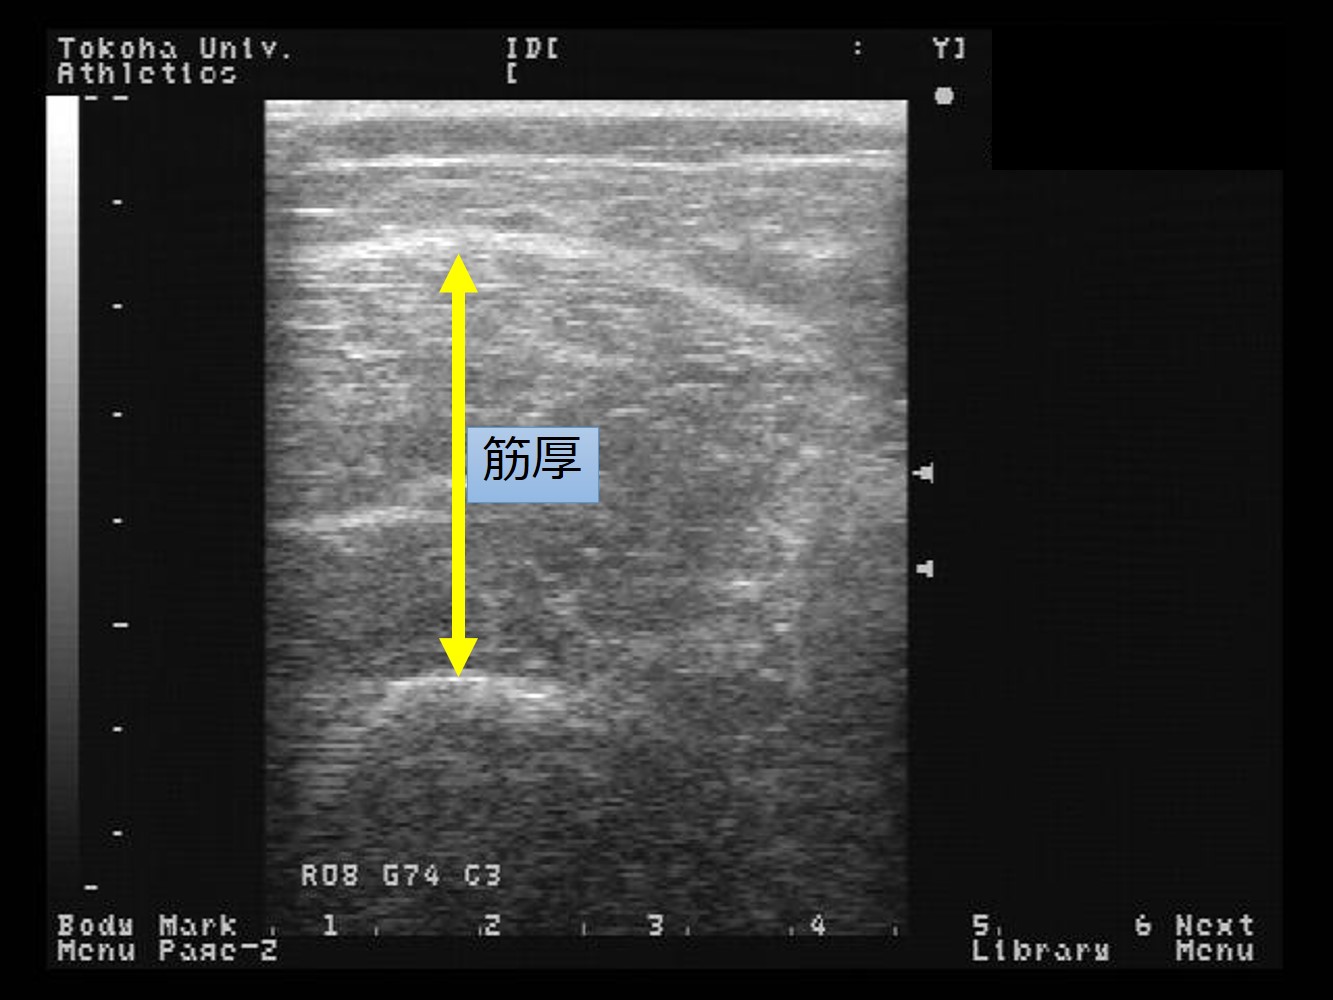

「形は力を産み、力は形を造る」という考え方から、アスリートに必要な骨格筋・腱複合体の形態や量と動作の関係について研究を行っています(骨格筋の筋厚、筋線維の羽状角、骨格筋の硬さ、動作分析[図1~4])。

図1